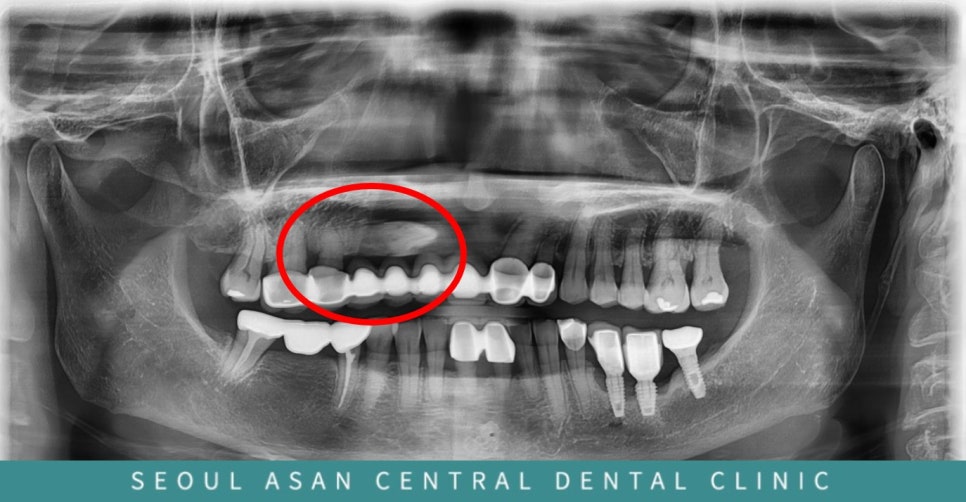

이 분은 오래전에 위에 오른쪽 어금니부터 앞니까지

총 치아 8개를 통으로 묶어서 만드신 이력이 있는 분입니다.

이렇게 길게 치아를 여러개 묶게 되면

남은 치아들에 너무 큰 힘이 가해지게 되며,

치아 하나가 망가지더라도

전체를 다시 치료해야하는 치명적인 단점이 있습니다.

그럼에도 이렇게 치료 받은 이유를 여쭈어 보니,

위 오른쪽 부위에 송곳니가 매복되어 있는데

위치가 너무 코랑 가까워서 고난도의 발치가 필요합니다.